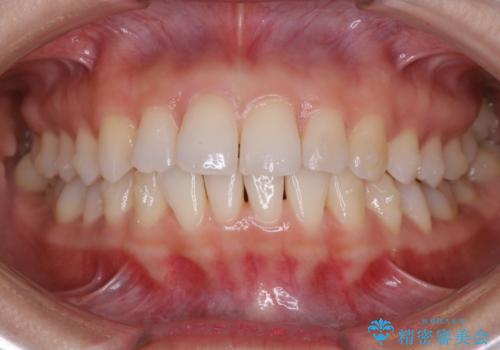

【非抜歯】前歯のガタつき マウスピースの部分矯正

- 上下の前歯の細かいガタつきの治療をご希望されて来院されました。

奥歯部分にはガタつきや噛み合わせの問題などがほとんど見られず、前歯のガタつきも軽度だったため、インビザライン ライト パッケージでの部分矯正を行うこととなりました。

今回のケースでは奥歯の噛み合わせに問題がほぼみられなかったため、前歯の位置のみに焦点を当て部分矯正を行いました。

適応されるケースが限られるものの、適応であった場合の治療期間は全体矯正と比べると格段に短くなり、費用も抑えられます。